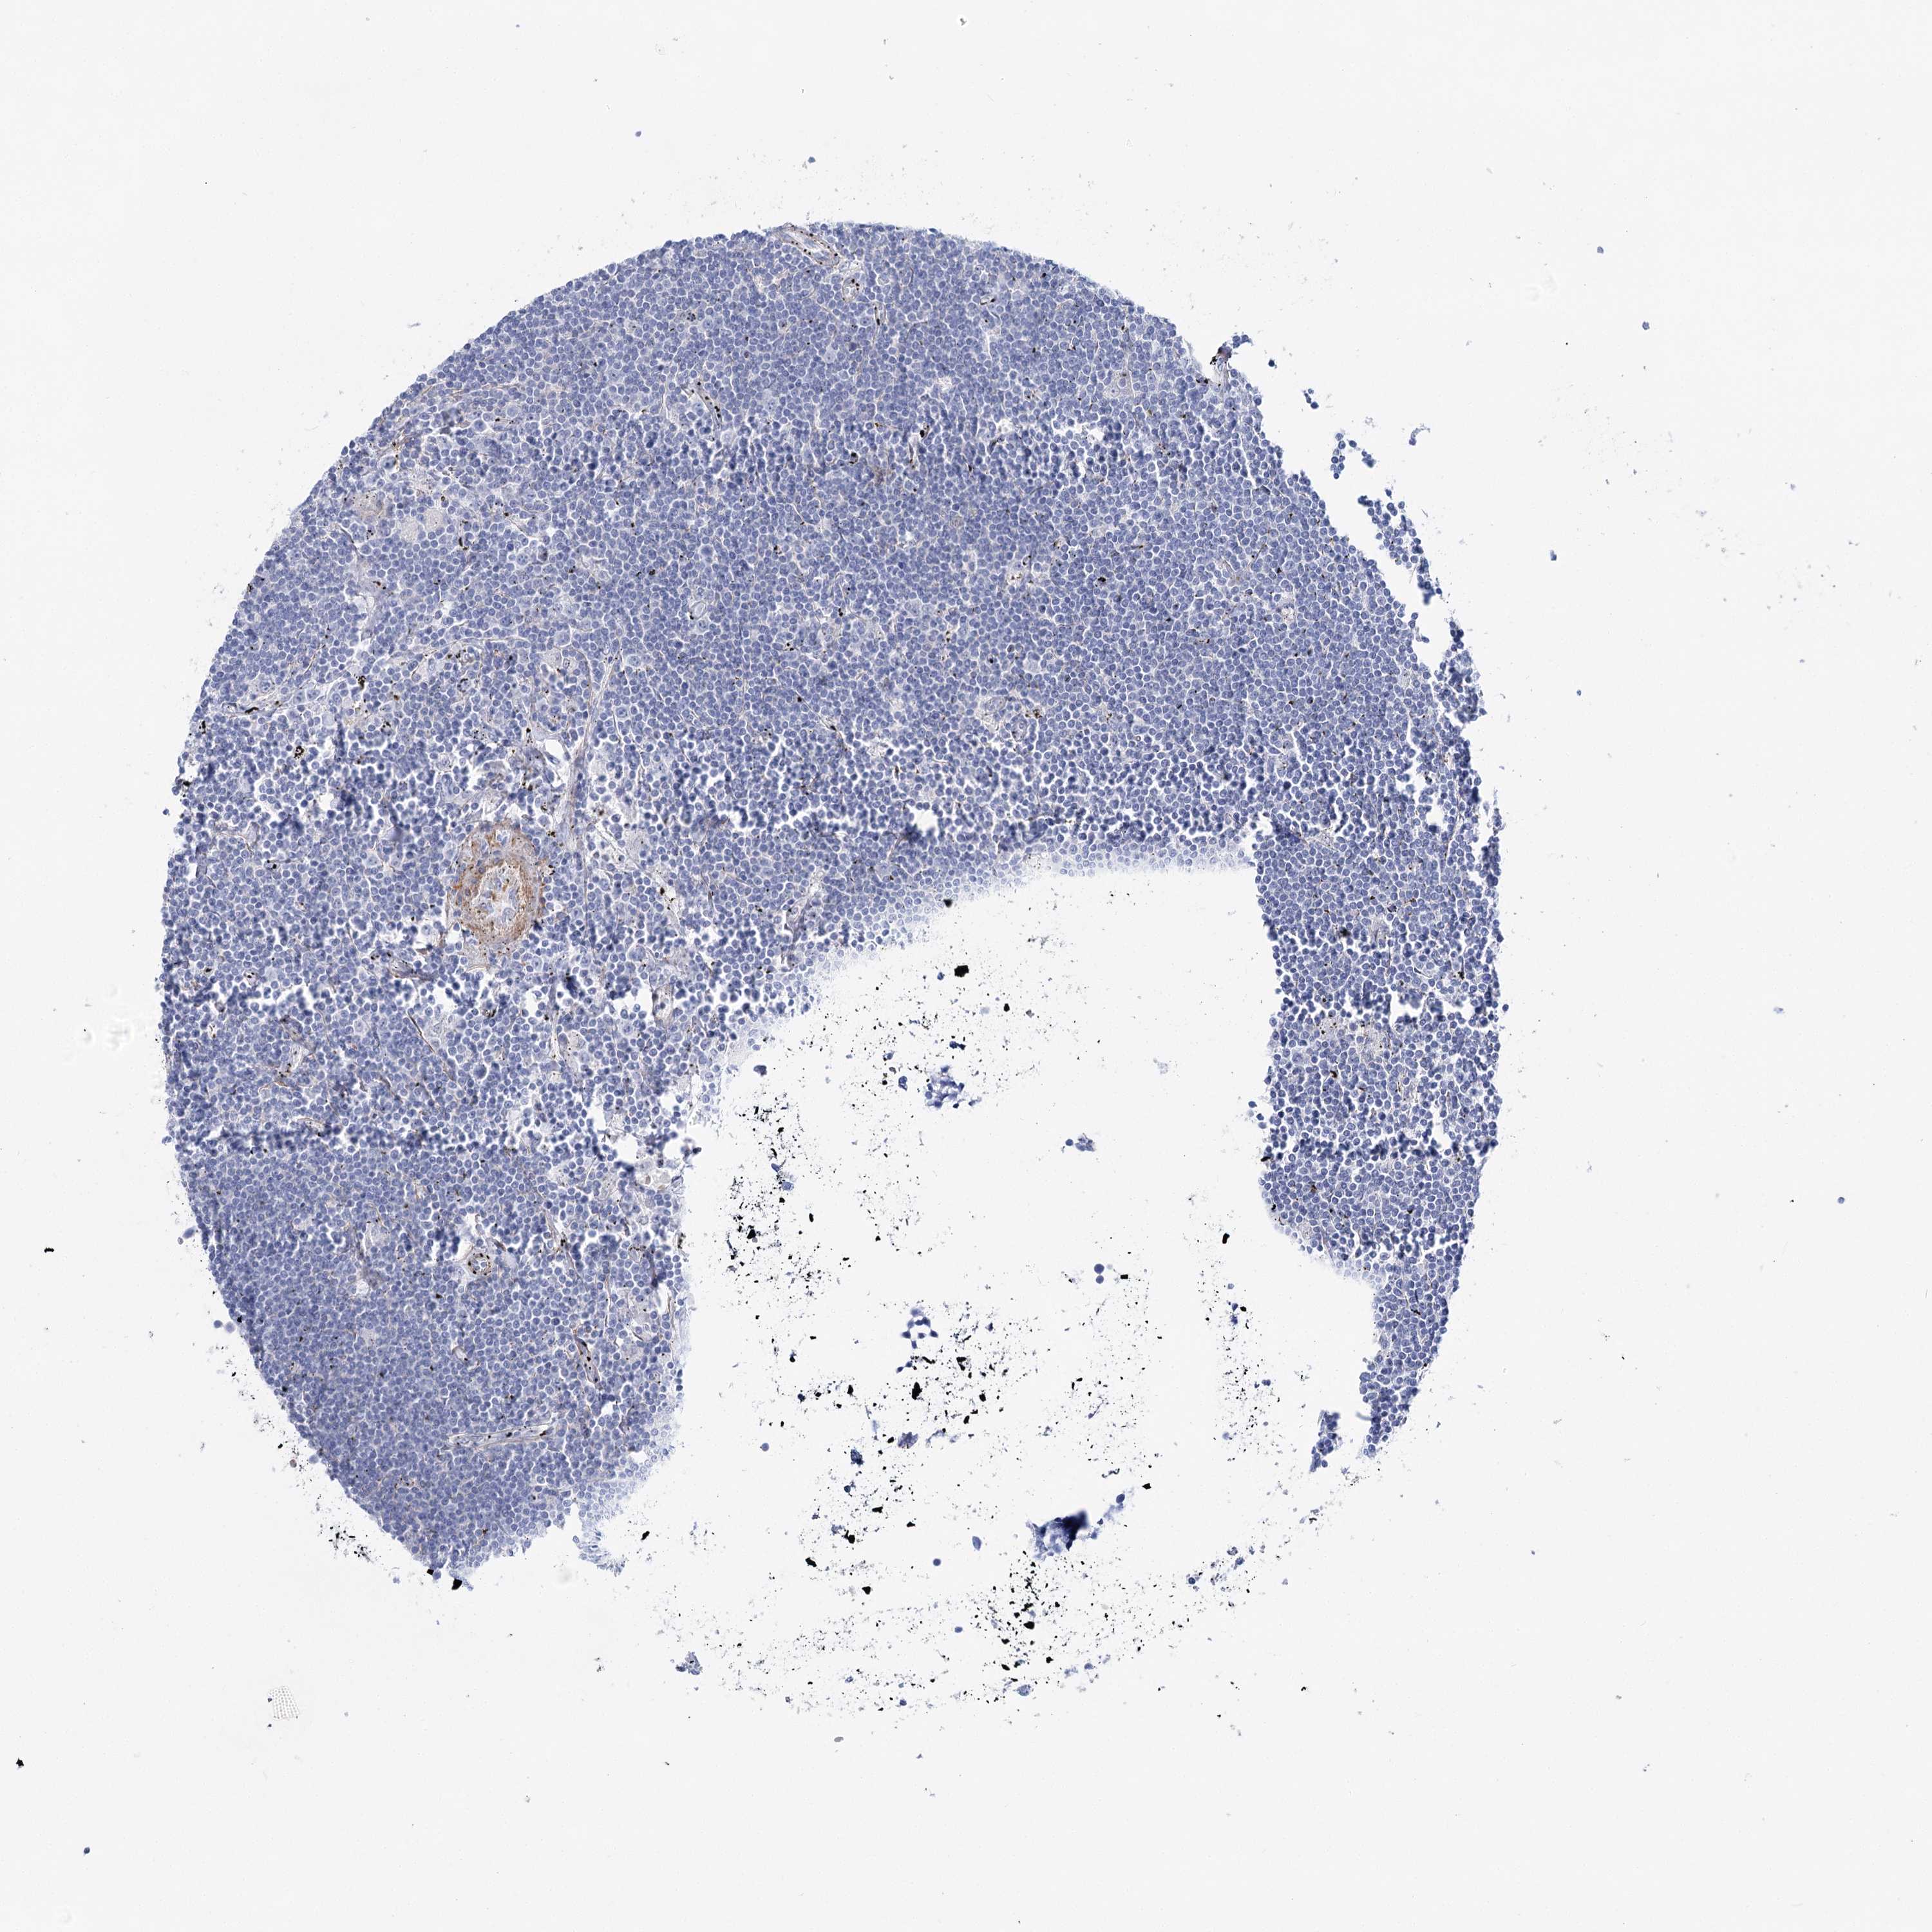

LYMPHOMA - Protein expressioni

A mouse-over function shows sample information and annotation data. Click on an image to view it in a full screen mode. Samples can be filtered based on level of antibody staining by selecting one or several of the following categories: high, medium, low and not detected. The assay and annotation is described here.

Each image is clickable and will lead to virtual microscopy that enables deeper exploration of all samples and also displays staining intensity scores, fraction scores and subcellular localization as well as patient and tissue information for each sample.

Antibody HPA036201

Hodgkin's disease, NOS

Malignant lymphoma, non-Hodgkin's type, High grade

Malignant lymphoma, non-Hodgkin's type, Low grade